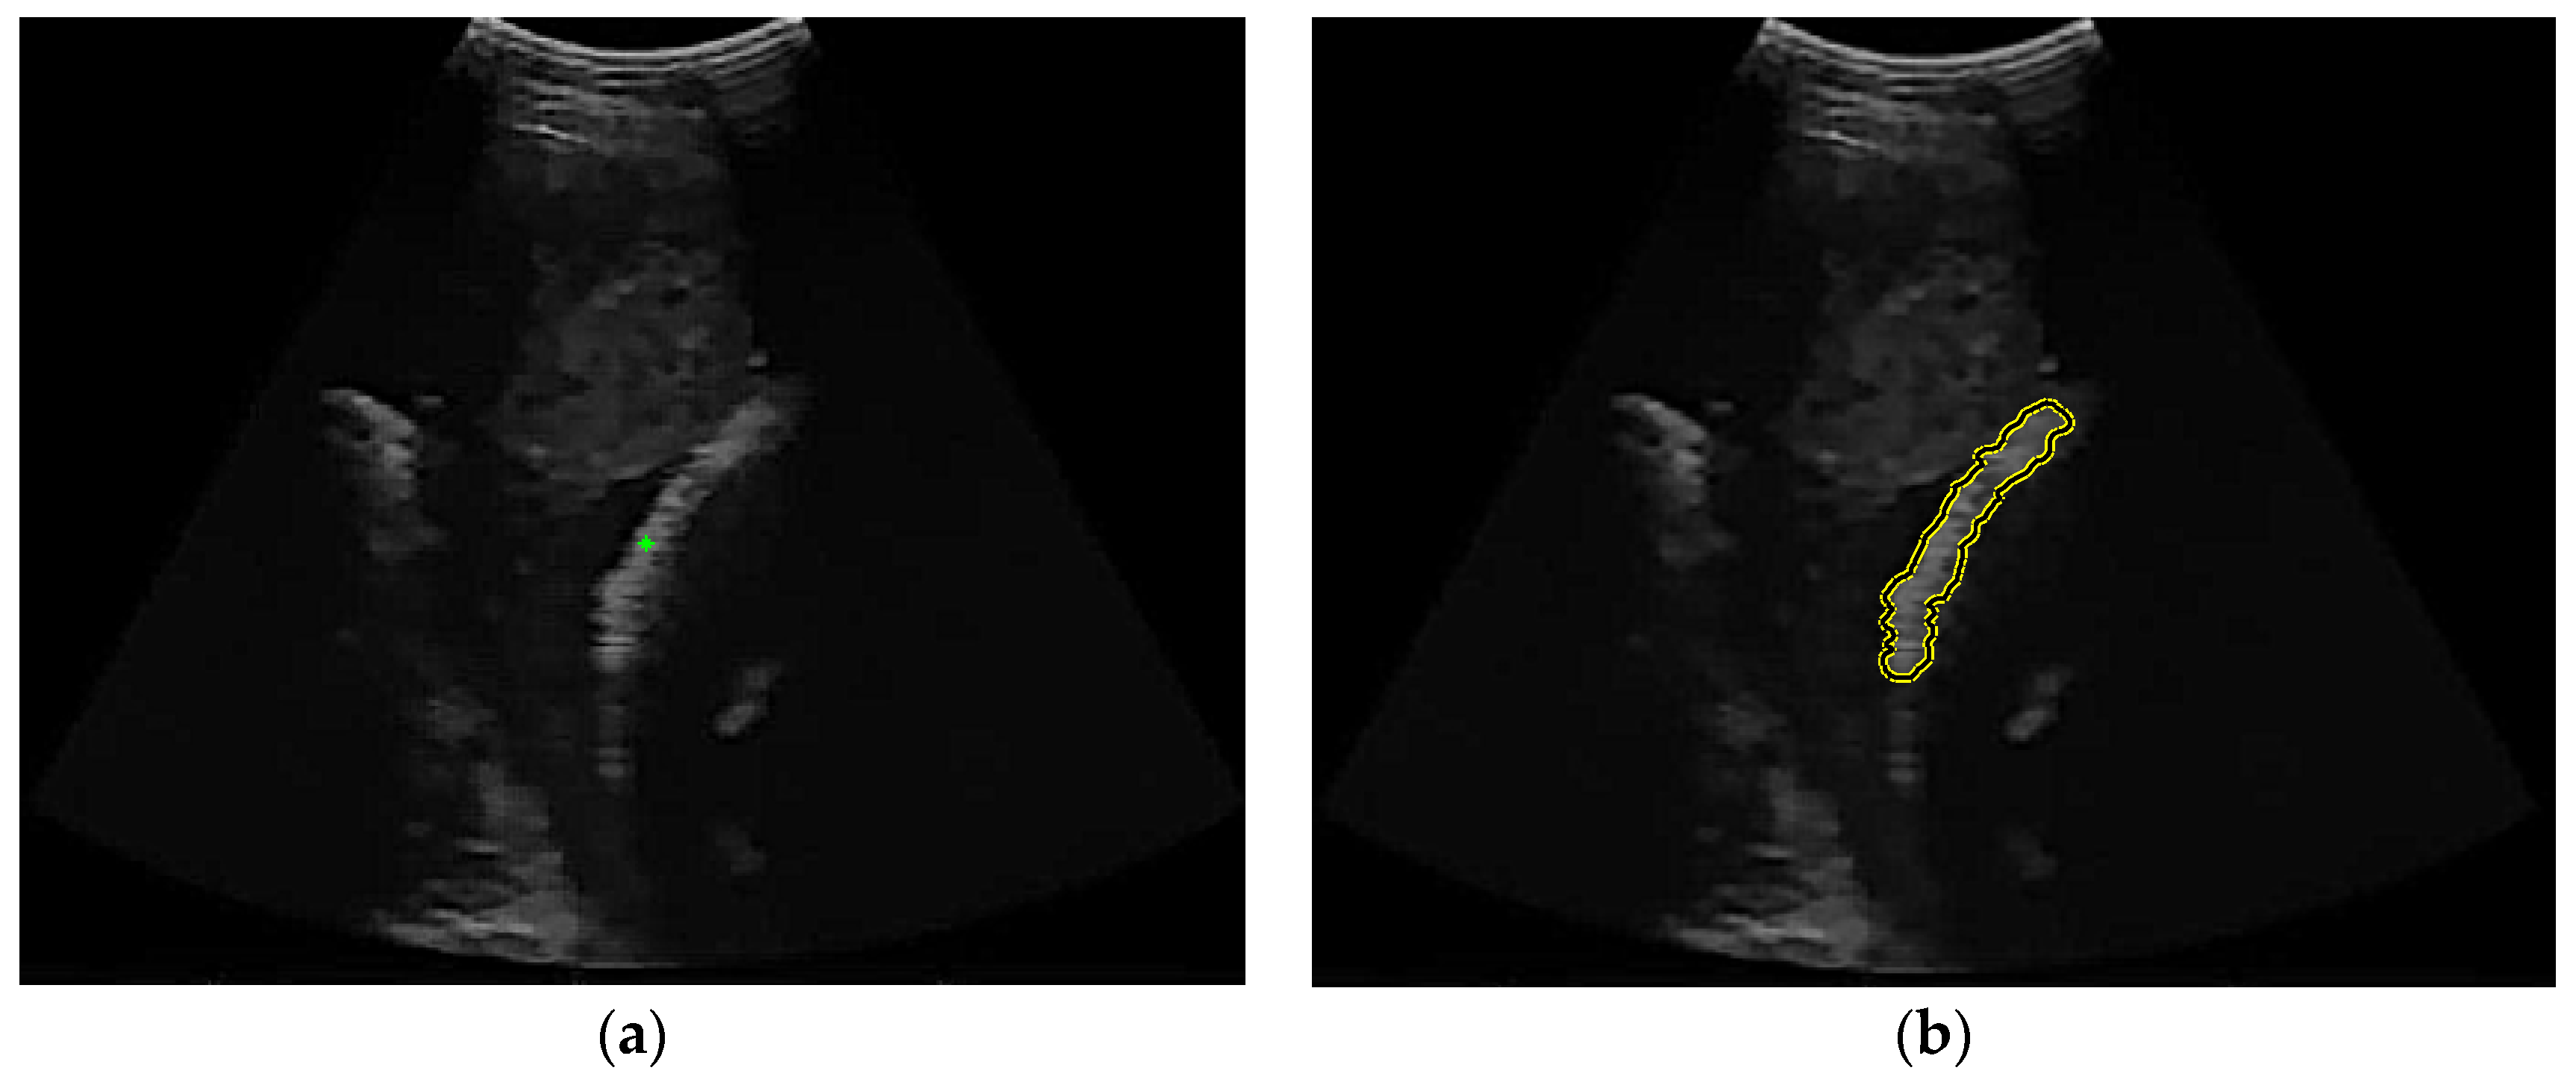

The femur ultrasound image captured by portable ultrasound has low contrast and brightness, as shown in Figure 1(a). The distribution of the intensity histogram was unimodal and tended to accumulate in the low-intensity areas (Figure 1(b)). Therefore, the problem is how to extract the femur region with a small area and intensity that is not significantly different from the background area.

Figure 1. (a) An example of a femoral ultrasound image obtained from a portable scanner and (b) its histogram.